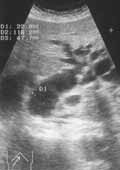

Наиболее частой причиной механической желтухи является холедохолитиаз (Рис. 2). Диагноз достоверен в случае определения в просвете холедоха гиперэхогенной структуры с акустической тенью. На основании этого ультразвукового признака конкременты выявляются лишь в 30-35 % случаев. Относительно невысокий процент обнаружения камней в просвете протока при УЗИ объясняется тем, что в большинстве случаев обтурацию вызывают камни, находящиеся в дистальном отделе холедоха, визуализация которого затруднена из-за ретродуоденального расположения.

Увеличить

Рис. 2. Холедохолитиаз. Конкремент в просвете холедоха (стрелка). Расширены внутрипеченочные желчные протоки (кадр слева).